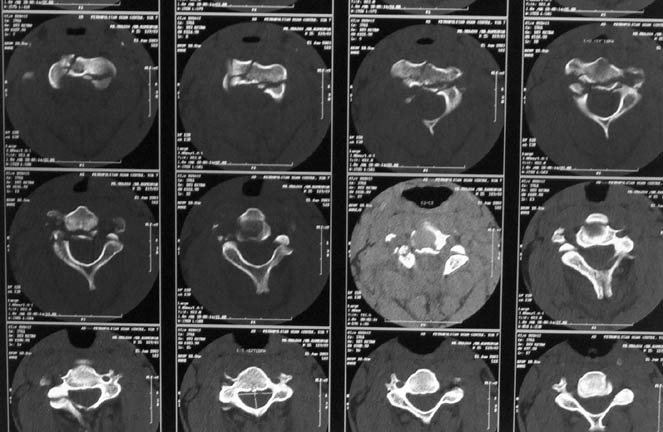

At our centre: Haemodynamically stable. Grade III compound fracture left femur with a wound anteromedially in the middle thigh through which the femur had come out. Distal pulse present. Cervical spine - C1 post ring fracture right side. C2 fracture body with listhesis. No canal compromise. No neurological deficits clinically.

X rays and CT film attached. We have put the patient on skull traction and posted him for debridement and proceed ----. What we have done I would like to present after the discussion.

I was disappointed that there was not even one comment after the cervical spine dynamic views were presented. Though there is instability, the CT picture showed that the body of C2 was totally comminuted and hence a decision to keep the patient in Halo was taken by my colleague in charge of the spine unit. After the consolidation of the body of C2 if required he will go through a formal C2-3 fusion.